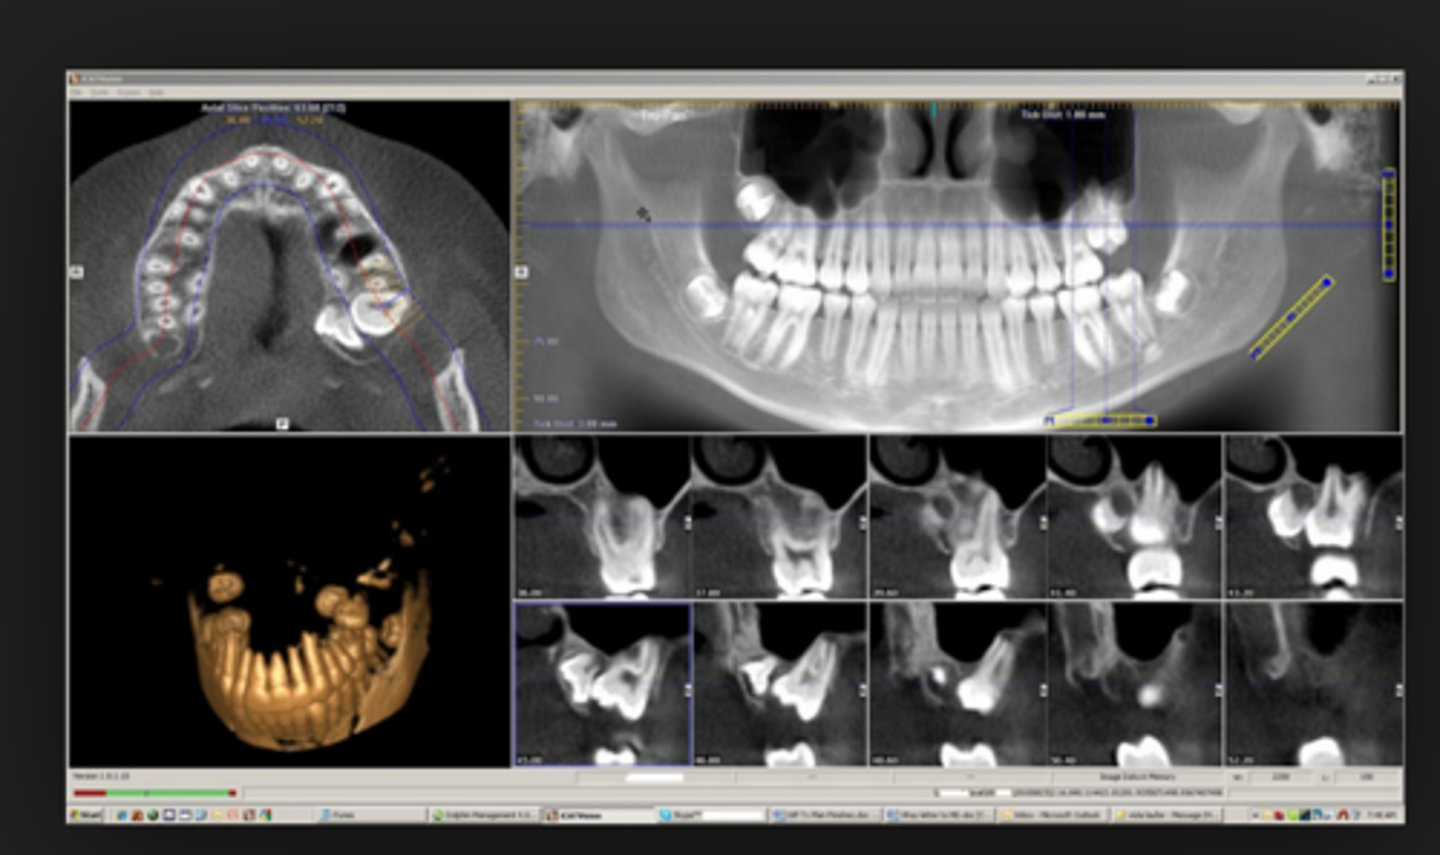

Computed tomography radiography function-

CBCT-Cone Beam Computed Tomography

takes a series of cross-sectional images using 3d information